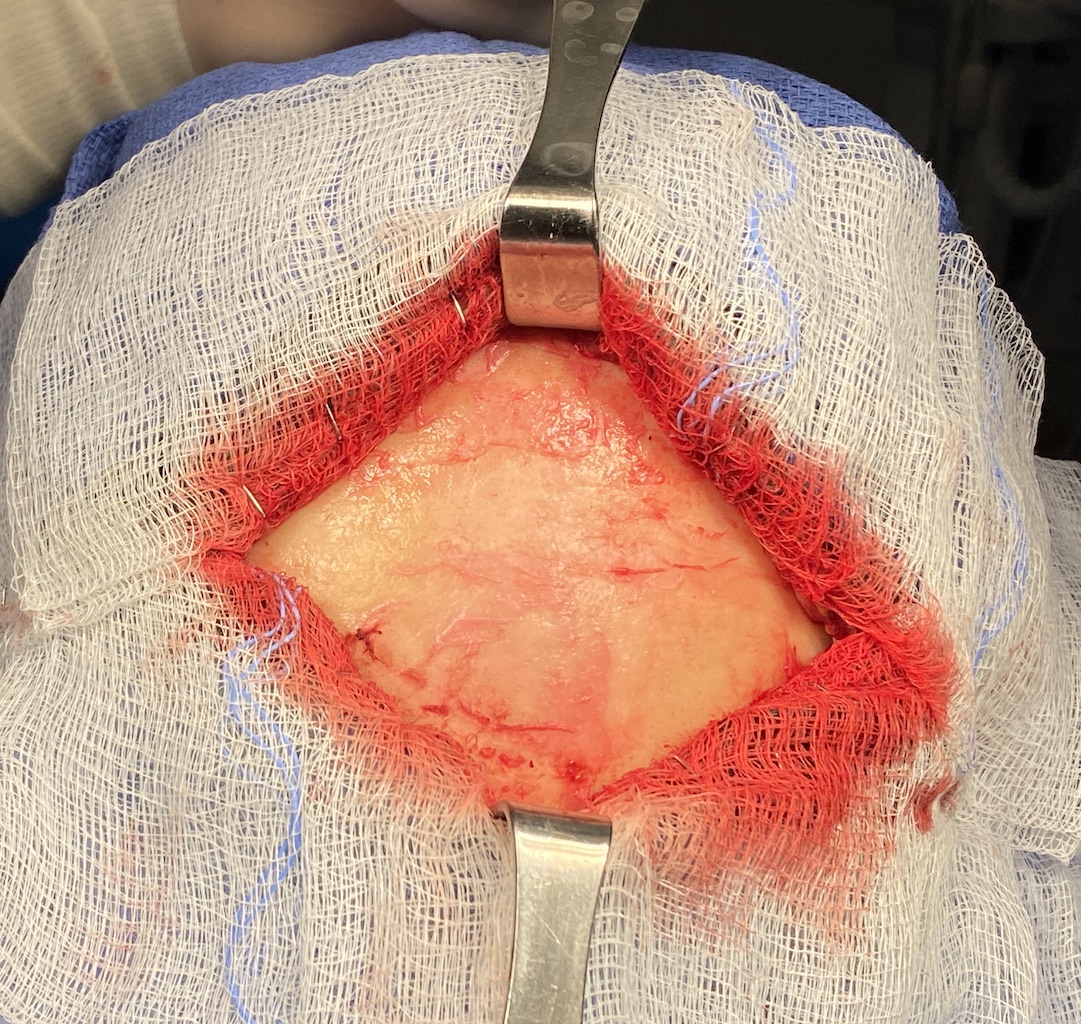

Patient 45

Desire for reduction in height of top of head.

Top of head skull reduction by removal of the outer cortical bone layered by a grid burring technique.

Desire for reduction in height of top of head.

Top of head skull reduction by removal of the outer cortical bone layered by a grid burring technique.